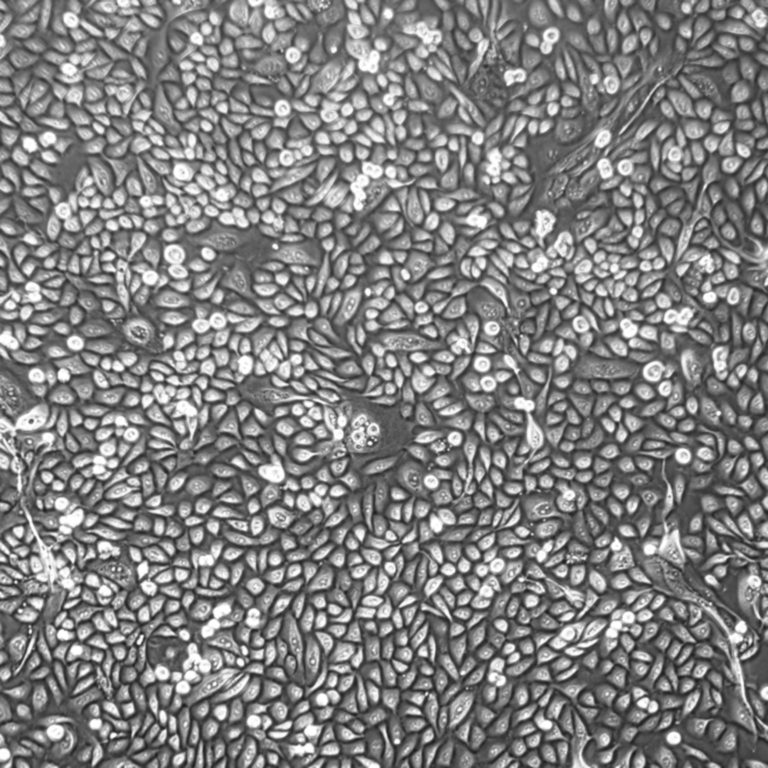

Human Prostate Epithelial Cells

Human prostate stock photo. Image of tissue, epithelium – 93292368